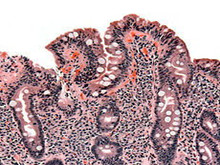

乳糜泻

(非热带脂肪泻、麦胶肠病、乳糜腹泻)

检查

血常规、粪便检测、活体组织病理检查(活检)